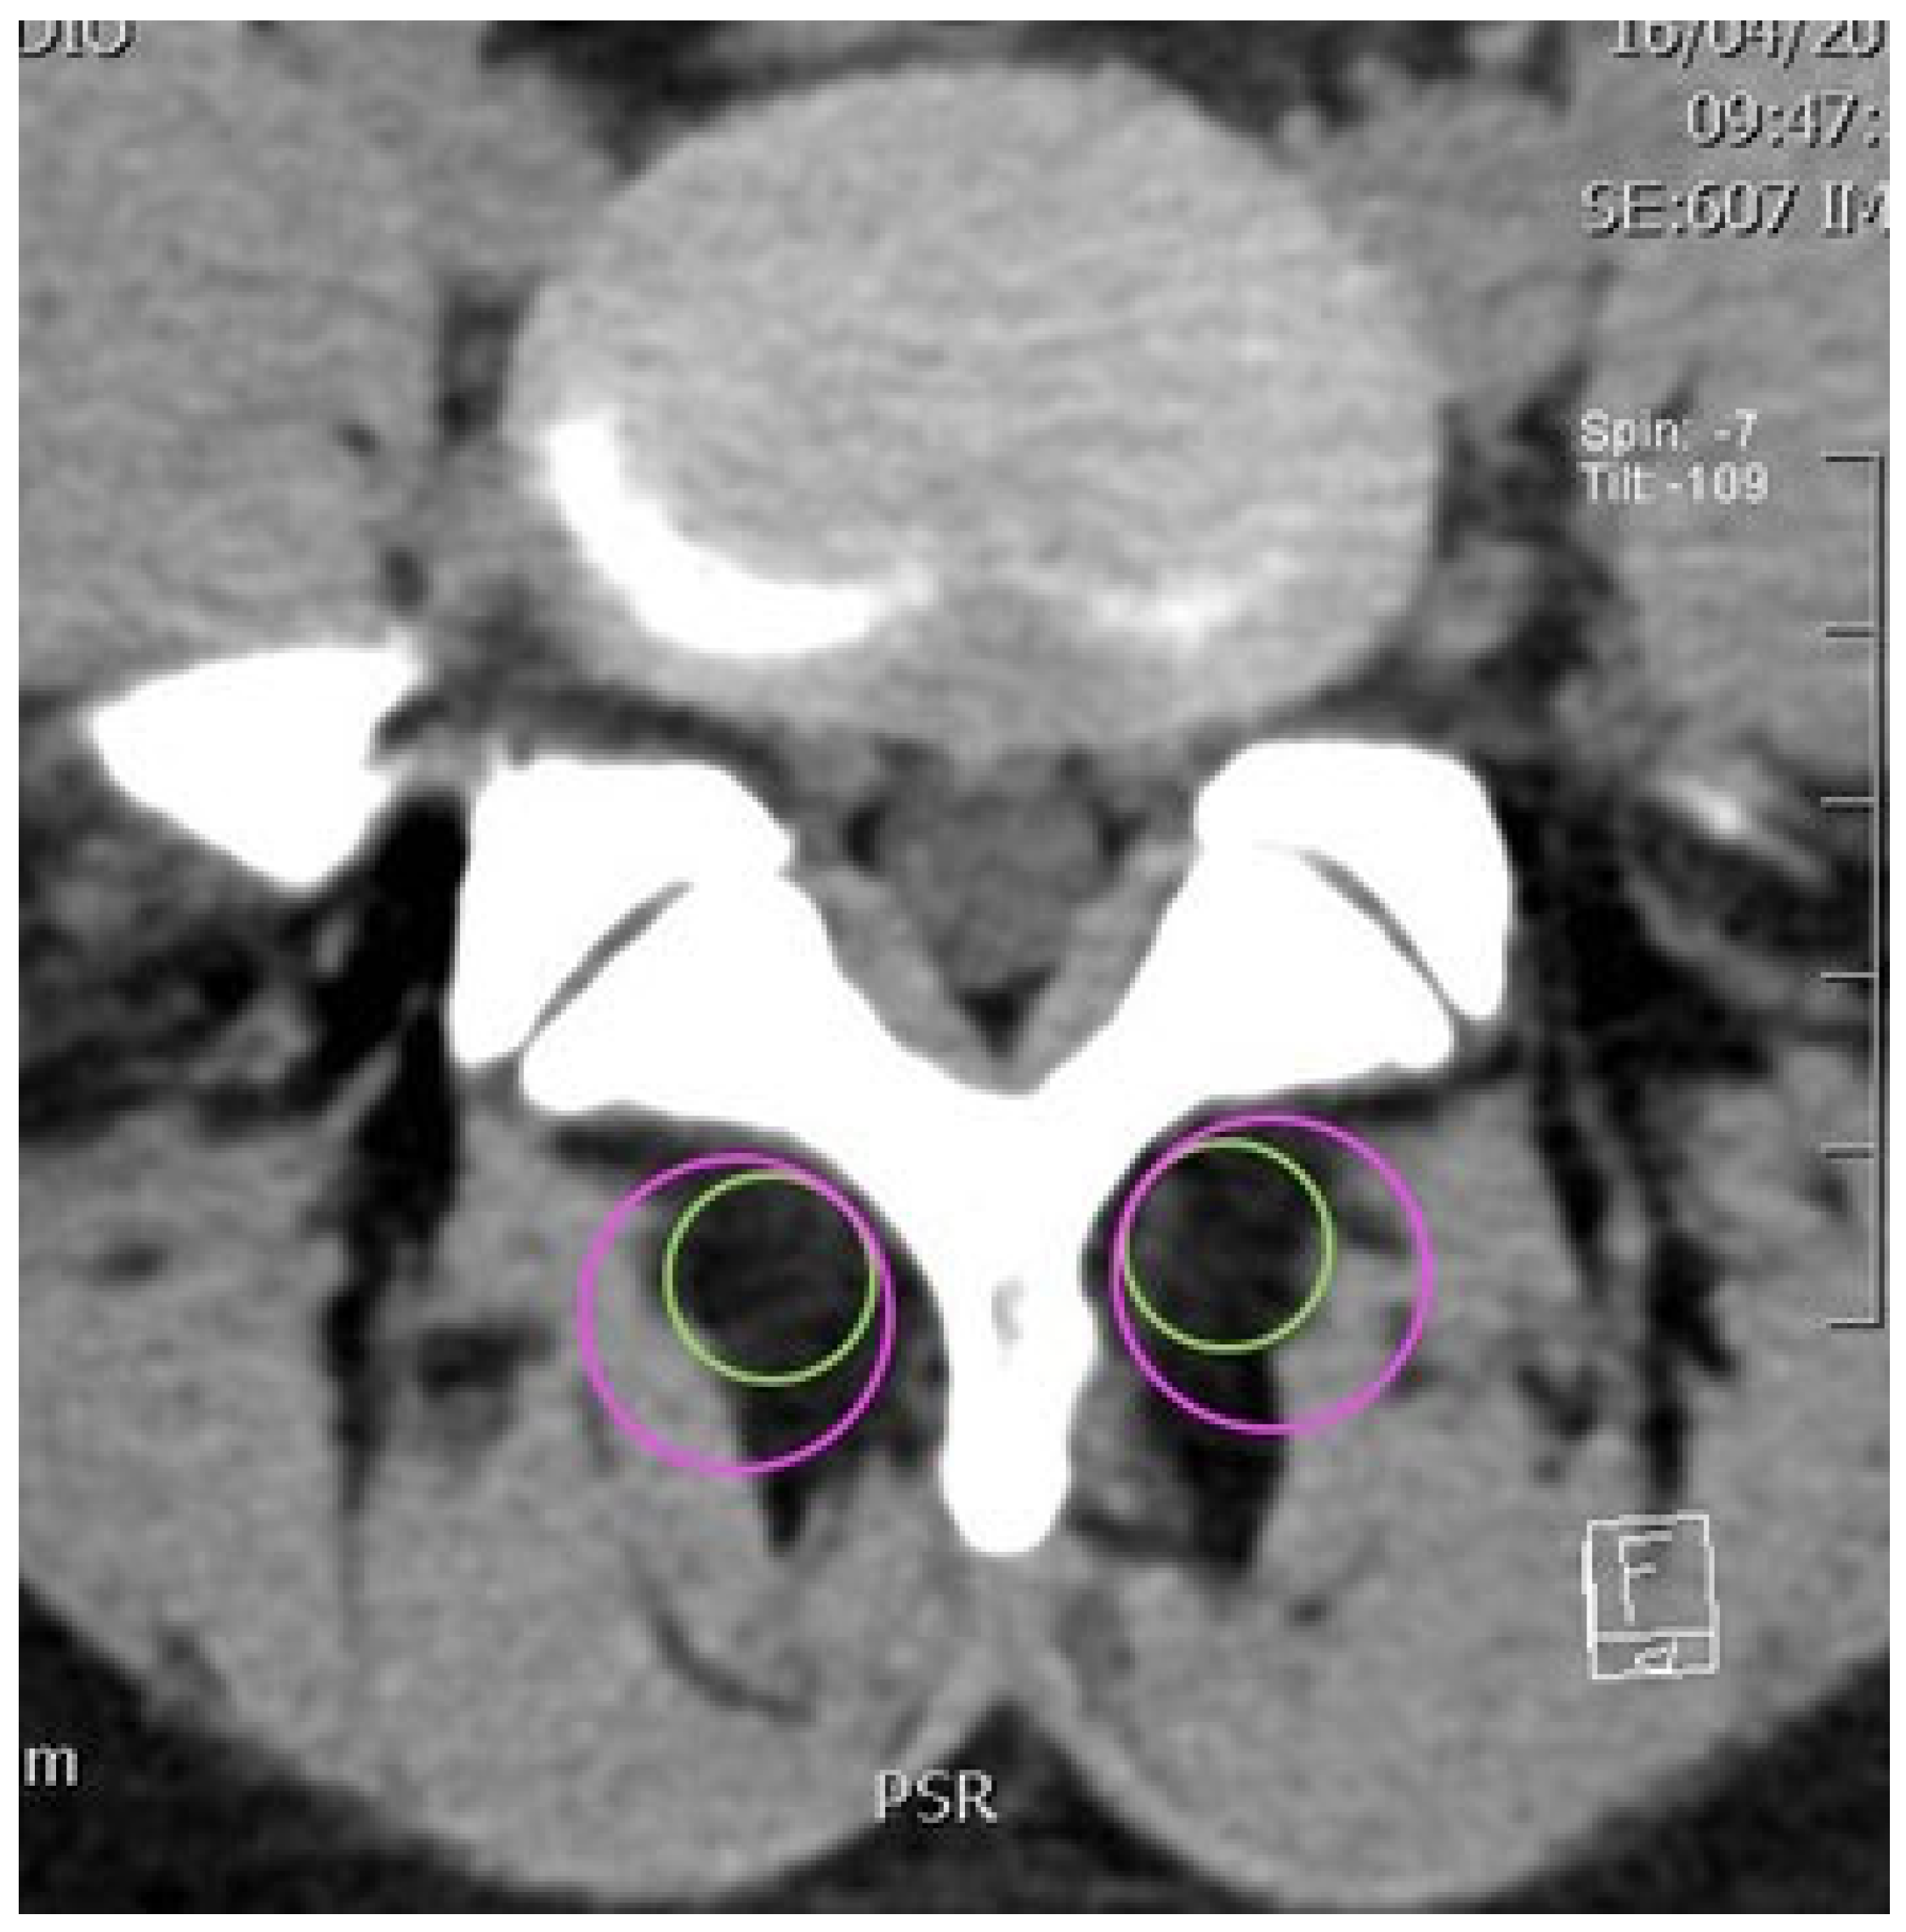

2.2. CT Imaging Research Methodology